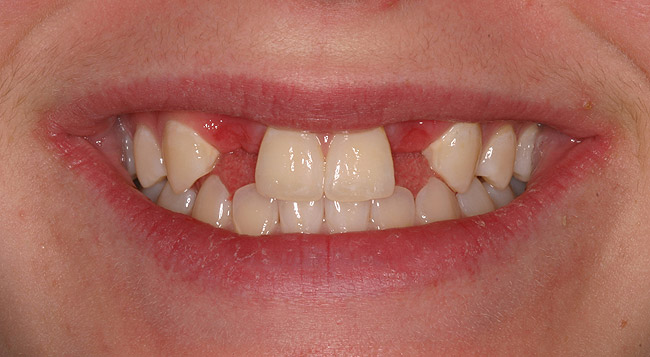

Figure 5a  Congenitally missing lateral incisors. Postorthodontic therapy, prior to implant placement.

Figure 5a

Figure 5b  Congenitally missing lateral incisors. Postorthodontic therapy, prior to implant placement.

Figure 5b